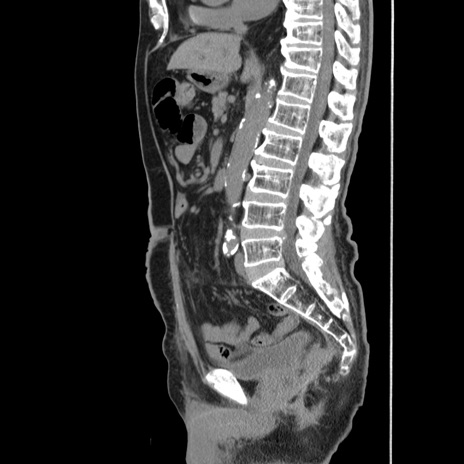

症例24(矢状断像)

【症例】80歳代男性

【主訴】左側腹部痛、嘔吐

【現病歴】本日早朝より左腹部に痛みあり。昼頃嘔吐認めたため、救急要請。

【既往歴】直腸癌(Mile手術)、胆摘

【身体所見】意識清明、BT 35.9℃、BP 221/93mmHg、SpO2 97%(RA) 、腹部:左ストーマ周囲に限局性の腹部膨隆あり。 膨隆部自発痛・圧痛あり・軟。

【データ】WBC 7700、CRP 0.09